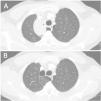

A 45-year-old man, current smoker came to the emergency department after a self-limited episode of mild hemoptysis (less than 30ml). No other symptoms were associated. Chest tomography showed right paratracheal opacity with bilateral adenopathies. As neoplasm and infection was suspected, bronchoscopy was later performed with negative cytology. All microbiological studies were also negative. A prolonged empirical antibiotic treatment was then maintained with satisfactory radiological progression (Fig. 1). The final diagnosis was infected azygos lobe bulla.